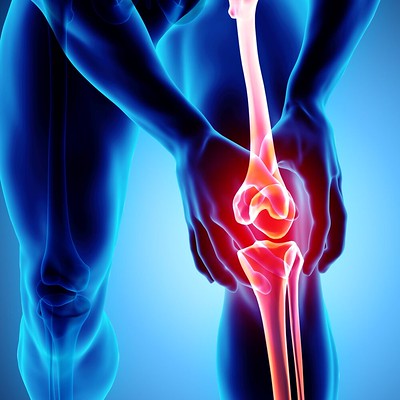

휴식 및 냉찜질

무릎을 휴식하고 해당 부위에 냉찜질을 하면 통증과 부기를 줄이는 데 도움이 될 수 있습니다. 얼음찜질은 한 번에 20분씩 하루에 여러 번 해야 합니다.

물리 치료

물리 치료는 무릎 관절 주변의 근육을 강화하여 통증을 줄이고 이동성을 향상시키는 데 도움이 될 수 있습니다.

의약품 아세트아미노펜 및 이부프로펜과 같은 처방전 없이 구입할 수 있는 진통제는 통증과 염증을 줄이는 데 도움이 될 수 있습니다. 더 심한 통증에는 처방약이 필요할 수 있습니다.

주사 요법

코르티코스테로이드 주사는 무릎 관절의 염증을 줄이는 데 도움이 되어 통증 완화에 도움이 될 수 있습니다.

수술 인대 또는 반월상연골 파열과 같은 보다 심각한 무릎 부상의 경우 수술이 필요할 수 있습니다. 진행된 관절염의 경우 무릎 교체 수술이 필요할 수 있습니다.

교정기 및 지지대

교정기와 지지대는 무릎 관절에 안정성을 제공하고 통증과 염증을 줄이는 데 도움이 될 수 있습니다.

무릎 통증은 급성 부상, 만성 질환, 과용 등 다양한 요인에 의해 발생할 수 있습니다. 무릎 통증에 대한 가장 효과적인 치료 옵션은 통증의 근본적인 원인에 달려 있습니다. 휴식, 냉찜질, 물리 치료 및 약물 치료가 종종 무릎 통증을 치료하는 데 사용됩니다. 더 심한 경우에는 주사 요법과 수술이 필요할 수 있습니다. 또한 보조기와 지지대는 무릎 관절에 안정성을 제공하고 통증과 염증을 줄이는 데 도움이 될 수 있습니다.